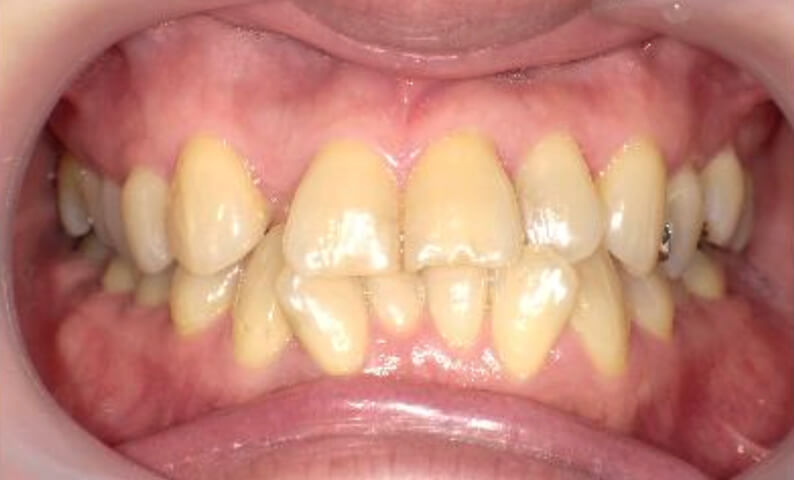

症例_030 上下顎の部分矯正

治療期間:12ヶ月金額:54万円+税女性八の字/V字型捻転歯前歯のガタガタ

| Before | After |

|---|---|

|